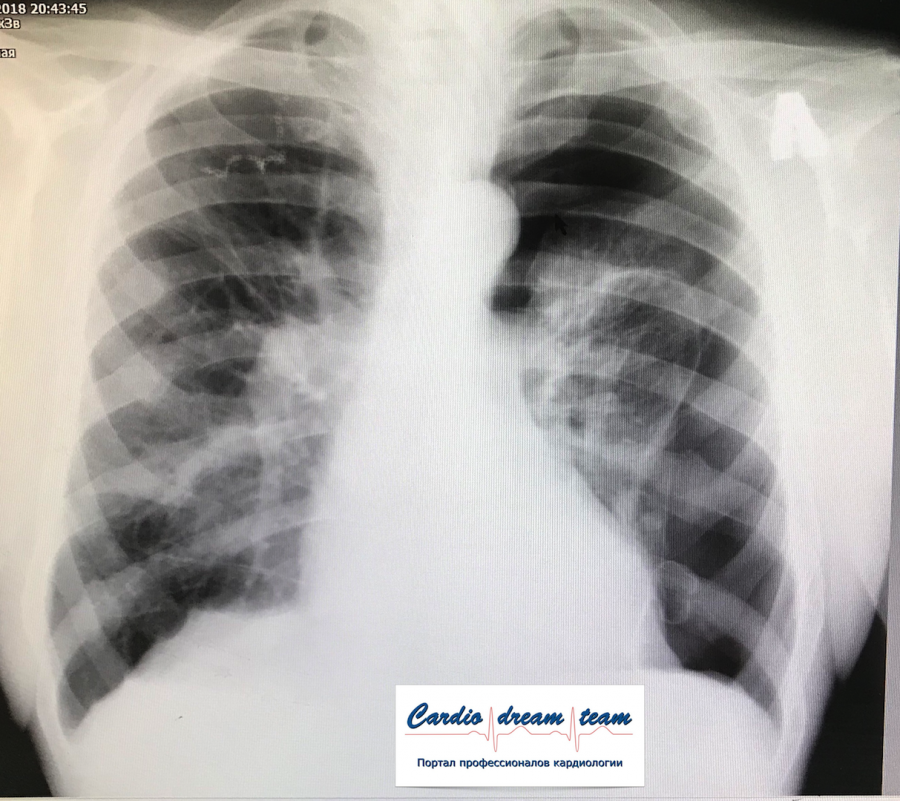

ИССЛЕДОВАНИЕ ОРГАНОВ ГРУДНОЙ КЛЕТКИ Дата 01-ОКТ-15 время 11.30 ОПИСАНИЕ: Проведена рентгенография органов грудной клетки в прямой проекции, положение сидя, условия ПИТ, Р-контроль Легочные поля: Справа легкое расправлено не полностью, апикально до 3го ребра прослеживается свободный газ в плевральной полости. Тень дренажа справа. Тень подключичного катетера в проекции ВПВ. Легочный рисунок: сгущен справа в прикорневой зоне, диффузно деформирован Корни: малоструктурны, обогащены Синусы: нечеткие Сердце: широко лежит на диафрагме (позиционно) ЗАКЛЮЧЕНИЕ: Течение правостороннего пневмоторакса, положительная Р-динамика. Состояние дренирования правой плевральной полости. Р-признаки полнокровия сосудов МКК. Пневмосклероз. Р-контроль .────────────────────────────────────────────────────────────────────── ИССЛЕДОВАНИЕ ОРГАНОВ ГРУДНОЙ КЛЕТКИ Дата 02-ОКТ-15 время 1015 ОПИСАНИЕ: